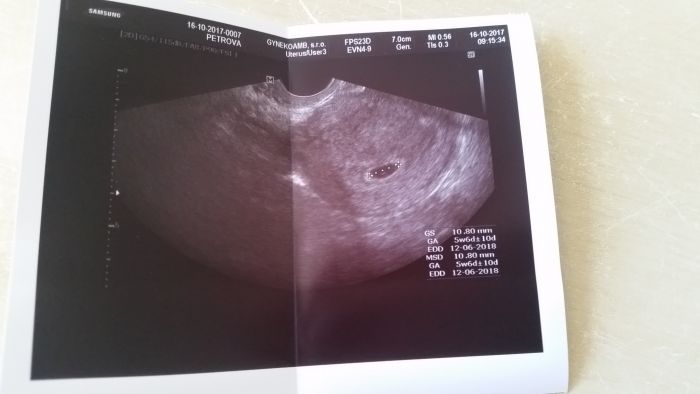

Ahoj holky mohu se k vám přidat? Včera jsem se dověděla že jsme v 6týdnu a termín podle UTZ 12.6 2018 a tady je naše malá "tečka"